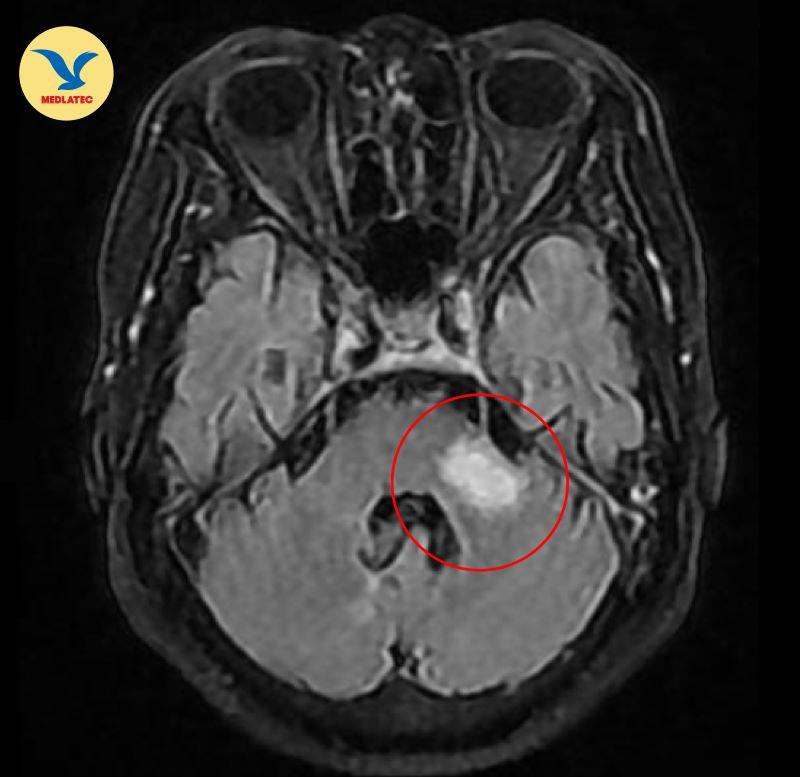

Tại viện, bệnh nhân được thực hiện các xét nghiệm, chẩn đoán hình ảnh chuyên sâu nhằm tìm chính xác nguyên nhân của các bất thường. Kết quả xét nghiệm của bà C. cho thấy chỉ số mỡ máu tăng cao, chụp MRI sọ não phát hiện hình ảnh nhồi máu não nhu mô cạnh sừng trán não thất bên phải, siêu âm tim cho thấy giãn nhĩ, hở van tim.

Kết quả chụp MRI sọ não phát hiện hình ảnh nhồi máu não nhu mô cạnh sừng trán não thất bên phải